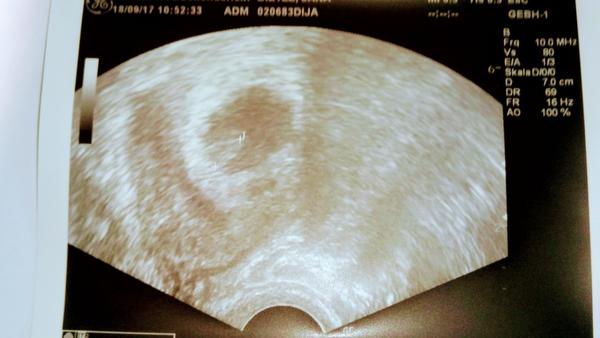

Tak jsme v poradku dnes 7+0 podle ultrazvuku. 6+6a srdicko tluce 😍

Jsme v poradku dnes 7+0 podle ultrazvuku 6+6 a srdicko tluce